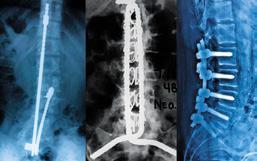

Implantes para la estabilización vertebral diseñados y aplicados en la Clínica de Columna. (Izq.) Rectángulo modelado con dispositivo de cierre “Codo de Dufoo”, (Centro) Sistema “SD” de instrumentación vertebral, (Der.) Implante para estabilización in situ de listesis lumbar L5/S1.

Sistema “SD” de instrumentación vertebral

Durante el periodo de estabilización vertebral con el uso de tornillos transpediculares, se presentaron dificultades con los tornillos de base fija, lo que obligaba a la recolocación frecuente del tornillo por no estar alineado con la barra. Con la aparición de los tornillos con base móvil, este problema se volvió menos frecuente. Sin embargo, consideramos que “el raquis del paciente debe ajustarse al perfil del implante”. Este criterio fue discutido con diferentes asesores de los centros de investigación mencionados previamente.

Por ello, diseñamos un sistema de barras sujetas con tornillos transpediculares, permitiendo que el ensamble sea ajustable al ángulo de colocación del tornillo transpedicular, a la curvatura vertebral, a la distancia interpedicular y a la distancia entre segmentos vertebrales. Con esta flexibilidad de orientación en los ensambles, logramos que el sistema de estabilización “SD” se adapte a la anatomía vertebral del paciente sin modificar la resistencia de la instrumentación ni forzar los ensambles. Resultados publicados.